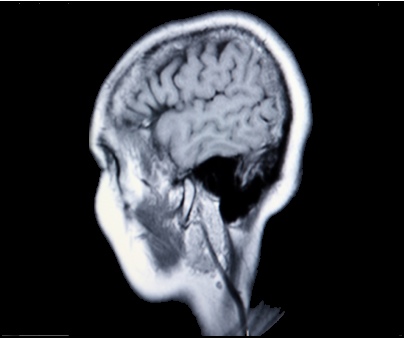

A new minimally-invasive procedure that can safely and effectively treat brain aneurysms without open surgery by implanting an FDA-approved device consisting of a flexible braided mesh tube made of platinum and nickel-cobalt chromium alloy directly into the artery has been chosen by research facility Cleveland Clinic as one of the top 10 medical innovations for 2012.

The platinum mesh tube can be delivered by catheter and used to block off large, giant, or wide-necked aneurysms in the damaged internal carotid artery. Platinum’s application in the medical field is extensive and the precious metal has long been used as cancer therapy.

6. Implantable Device to Treat Complex Brain Aneurysms